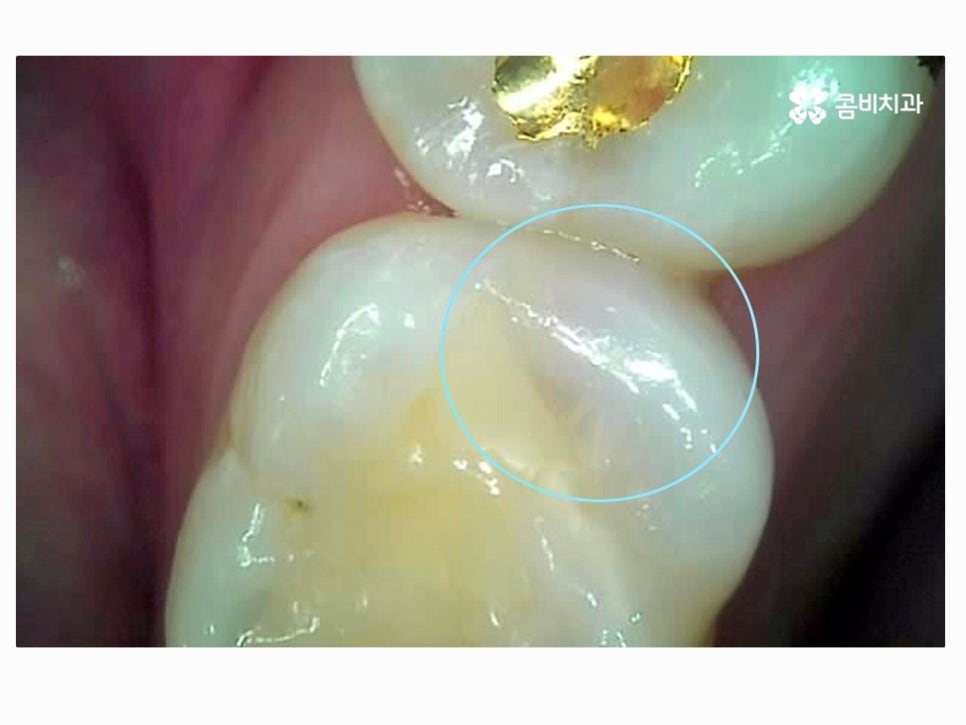

치아의 인접면 안쪽으로 내부 충치가 이미 깊어진 상황으로

평소에 치아 상태를 통증이나 겉으로 보이는 상태를 통해서만

체크를 한다면 충치가 심각해지거나 깊어지고 통증을 느끼지

않는다면 명동치과 치료 자체가 늦어지는 경우가 많이 있어요.

치아 사이는 음식물이 끼기 쉽고 이물질이 장기간 쌓이면서

치석으로 인한 충치, 잇몸질환 등을 겪기 쉽기 때문에

잘 보이지 않더라도 주기적인 검진이 필수적이며 평소 칫솔질 후

치실 혹은 치간 칫솔 사용을 꼭 해주실 필요가 있어요.